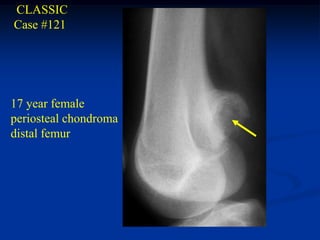

CLASSIC

Case #121

17 year female

periosteal chondroma

distal femur